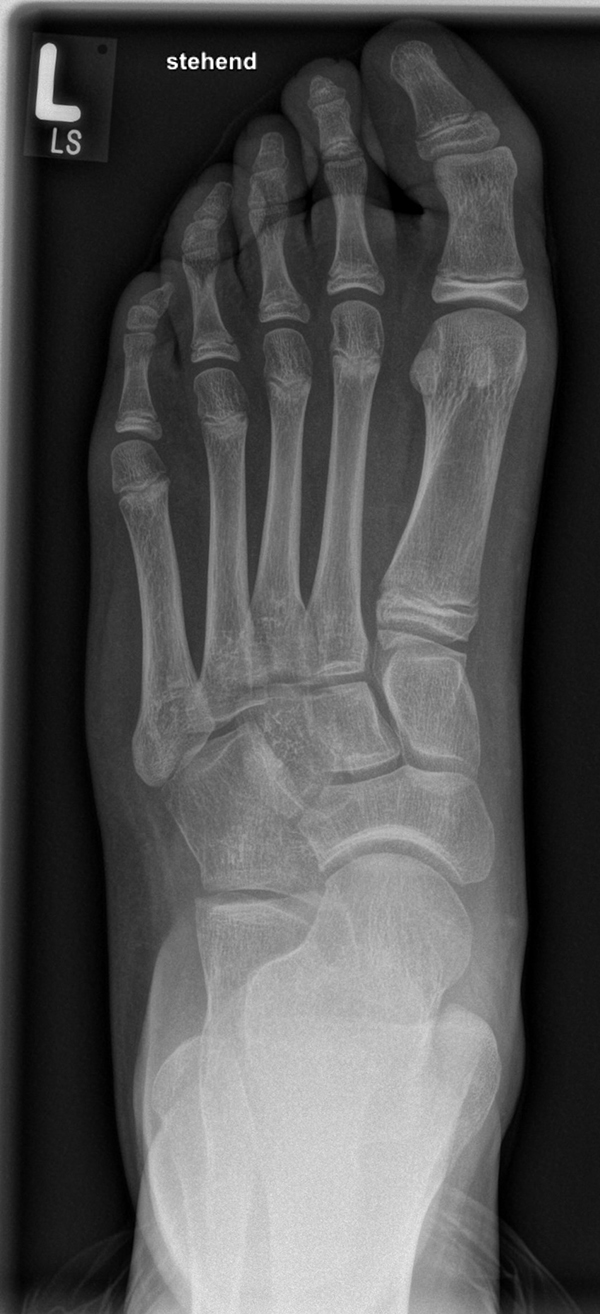

Abb. 2 a-c: offene Wachstumsfugen MT I Basis und Zehen (a), teilweise geöffnete Wachstumsfugen (b) und geschlossene Wachstumsfugen (c).

Die erforderlichen Osteotomien sind daher dem Fugenverlauf anzupassen, diese sind unbedingt zu respektieren. Wird eine Wachstumsfuge versehentlich mit der Fräse verletzt, kann durch partiellen oder kompletten Fugenverschluss ein Fehlwachstum provoziert werden. Achsabweichungen oder ein Wachstumstopp der betroffenen Region können die Folge sein. Offene Wachstumsfugen begrenzen die Osteotomieausrichtung besonders im Bereich des dorsalen Calcaneus, der Metatarsale I Basis und der IV. oder V. Zehe im End- und Mittelglied.